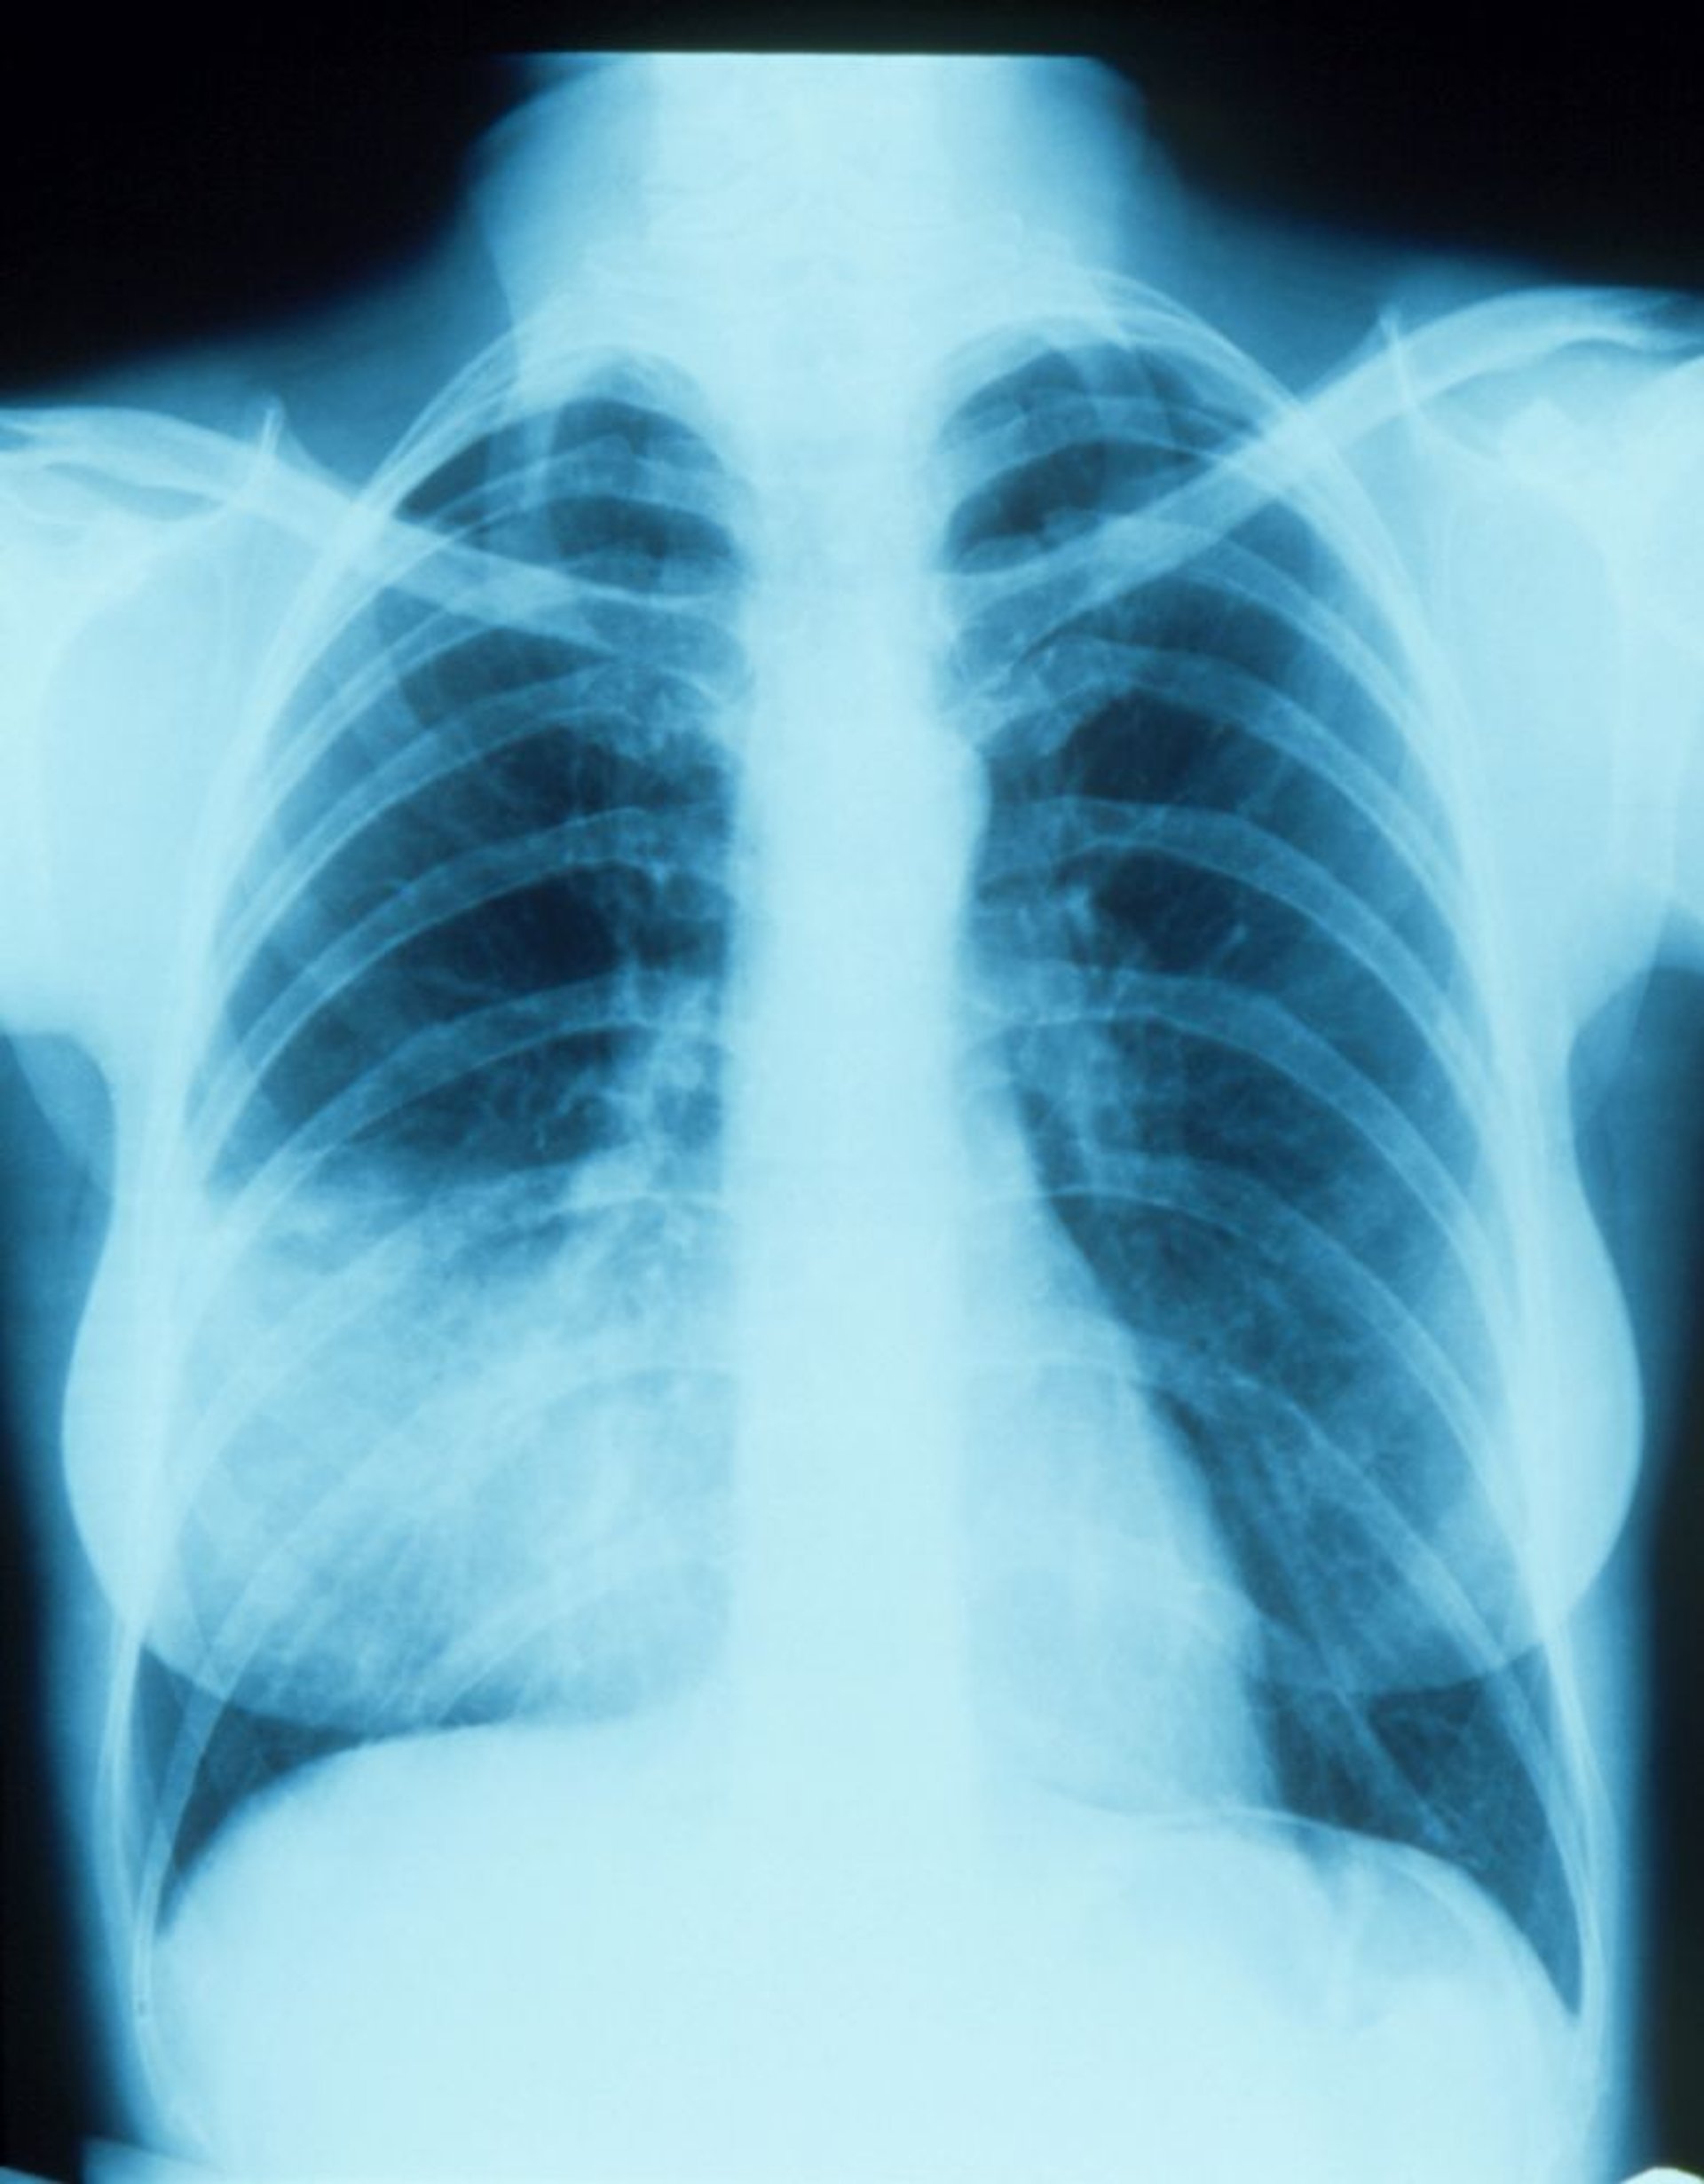

Пневмонія середньої долі справа з нечіткими контурами

This chest x-ray shows an infiltrate that appears to blend with the right heart border (silhouette sign). The silhouette sign indicates contiguous positioning of the 2 structures that have similar radiodensity; the part of the lung contiguous with the right heart border is the right middle lobe, so that is the part with the infiltrate and pneumonia.